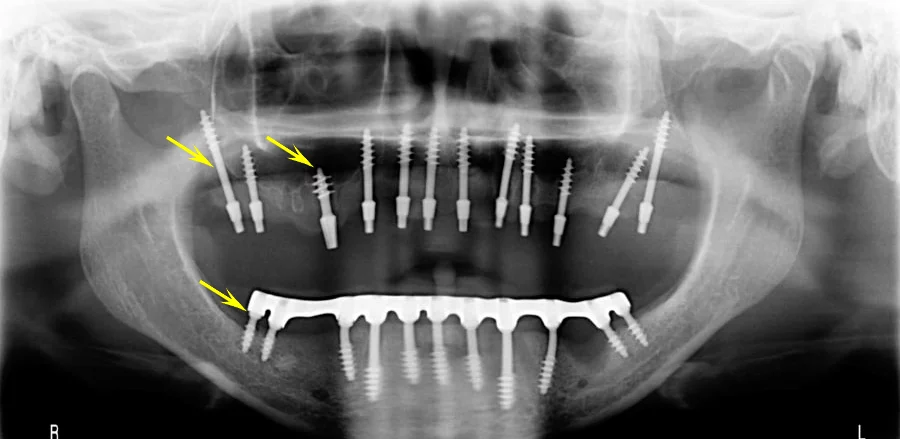

![]()

Если Вы считаете, что это прогнозируемая форма и именно пример базальной имплантация, то пусть будет базальная.

что через 2 года придется все менять

Очень благодарен за тему. Нет ничего лучше, что так компрометирует методику

А вот общий результат ужасен.